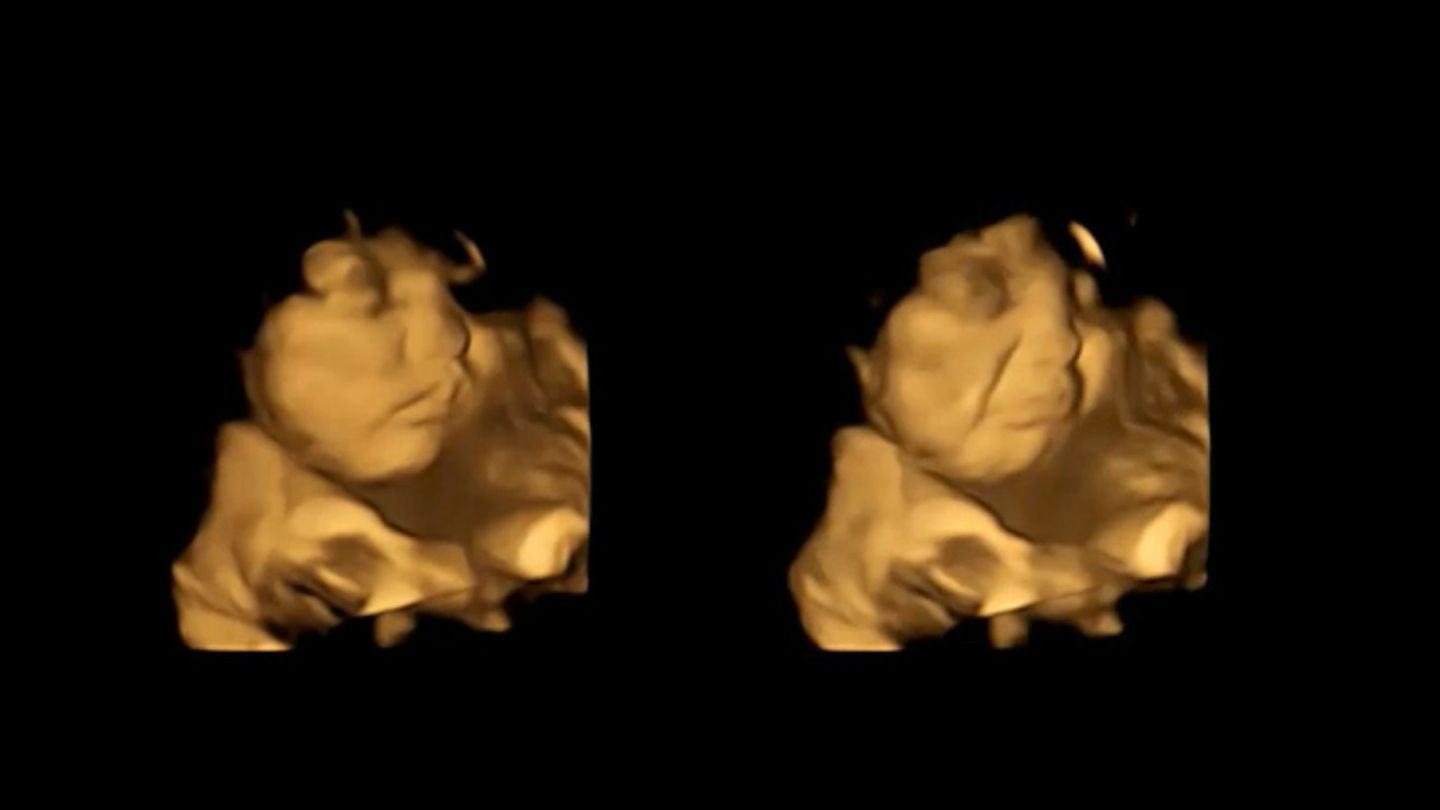

So hätten Föten ein eher "lächelndes Gesicht" gezeigt, nachdem ihre Mütter Karotten gegessen hätten, berichten Wissenschaftler der nordostenglischen Universität Durham in der Fachzeitschrift "Psychological Science". Nach dem Genuss von Kohlaromen hingegen hätten die Föten ein eher "weinendes Gesicht" gemacht.

Forschung mit 4D-Ultraschallaufnahmen

Die Forscher zeichneten mithilfe von 4D-Ultraschallaufnahmen bei 100 Frauen die Gesichtsausdrücke ihrer Babys in der 32. sowie 36. Schwangerschaftswoche auf. Die Mütter erhielten rund 20 Minuten vor dem Scan eine Kapsel mit rund 400 Milligramm Karotten oder 400 Milligramm Kohlpulver und nahmen zudem eine Stunde zuvor nichts zu sich, das Geschmack enthält. Gesichtsreaktionen der Föten wurden mit denen einer Kontrollgruppe verglichen, die weder Karotten noch Kohl erhalten hatten. Ergebnis: Selbst kleine Mengen mit Karotten- oder Kohlgeschmack reichten aus, um eine Reaktion auszulösen.